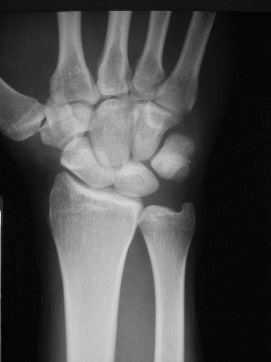

These are some of the main ligaments in the wrist.  These ligaments hold the small bones of the wrist together to themselves and to the end of the radius and ulna.  These ligaments serve a very important function for the wrist.  When these ligaments are injured they can cause significan dysfunction to the wrist.